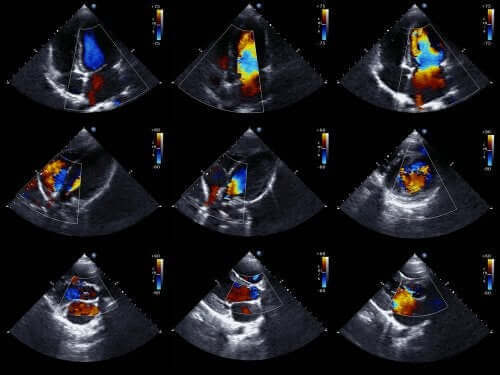

عادةً ما يستطيع الأطباء تشخيص هذا النوع من العيب الخلقي قبل ولادة الطفل. للقيام بذلك، يستخدمون مخطط صدى القلب للجنين. هذه تقنية تستخدم الموجات الصوتية لإعادة إنشاء صورة قلب متحركة.

وبفضل هذا، يمكننا أن نرى مظهر القلب ونفحص وظائفه عندما يكون الطفل لا يزال في الرحم. باستخدام هذه المعلومات، يمكن للأطباء وضع برنامج علاجي بعد الولادة مباشرة.